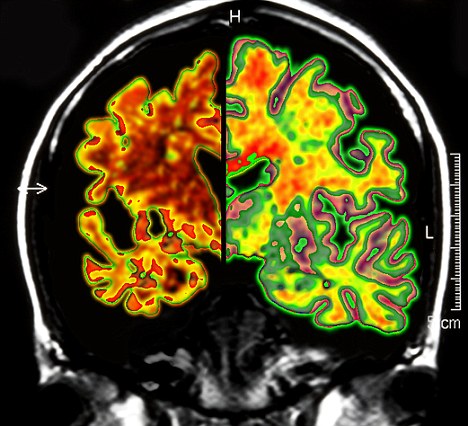

其實(shí)早在2010年,加拿大就已經(jīng)對(duì)這種大腦“起搏器”展開(kāi)臨床試驗(yàn)。當(dāng)時(shí),有6名輕微老年癡呆癥患者參加。當(dāng)時(shí)的試驗(yàn)結(jié)果顯示,在13個(gè)月的觀察期中,這些病患的葡糖糖代謝速度持續(xù)上升,這也就說(shuō)明他們的大腦神經(jīng)元正在工作。而在同時(shí)期內(nèi),大部分老年癡呆癥患者的葡萄糖代謝水平則是在不斷下降。